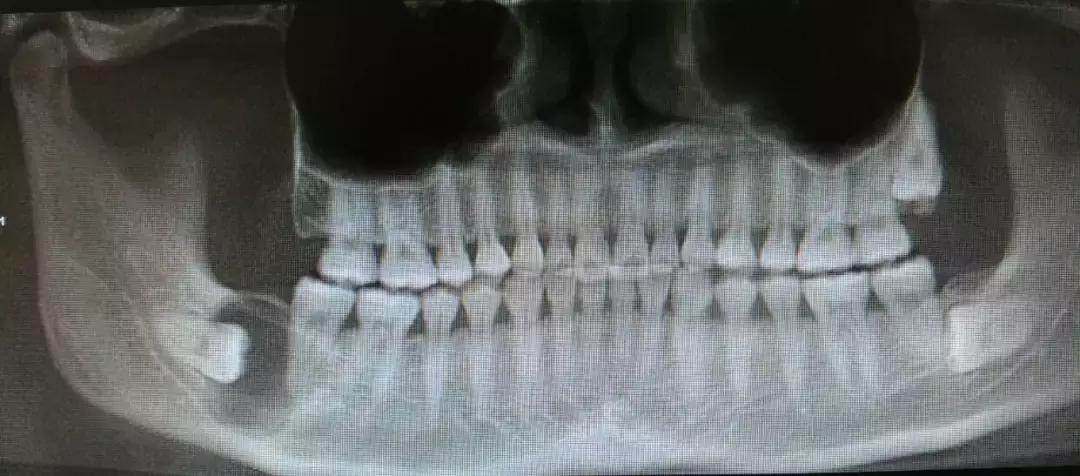

这种情况的智齿,牙片长这样↓

吃点东西就咬腮帮子或智齿反复摩擦颊粘膜↓

智齿因阻生疑为不明原因神经痛

或可疑病灶牙时

阻生智齿和神经的关系↓

对待这种「骑」在神经上的智齿要以医生建议为主,即使拔也一定要选择微创拔哦。这个危险距离,一锤子下去,神经可就很难保住了。